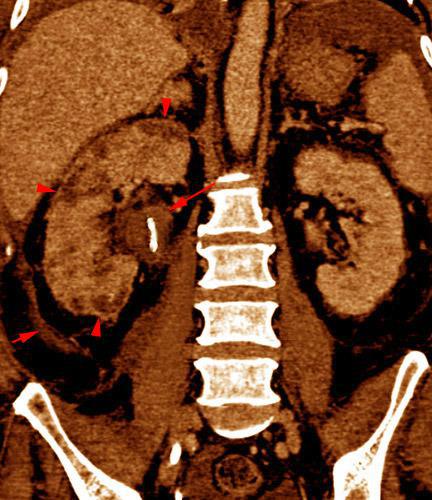

Abscesos renales en pionefrosis

VR seccional. Visión coronal anterior. Nefromegalia. Obstrucción renal derecha con catéter doble J (flecha larga). Múltiples lesiones hipodensas (puntas de flecha) correspondientes a abscesos renales. Obsérvese el engrosamiento de la fascia de Gerota (flecha corta)